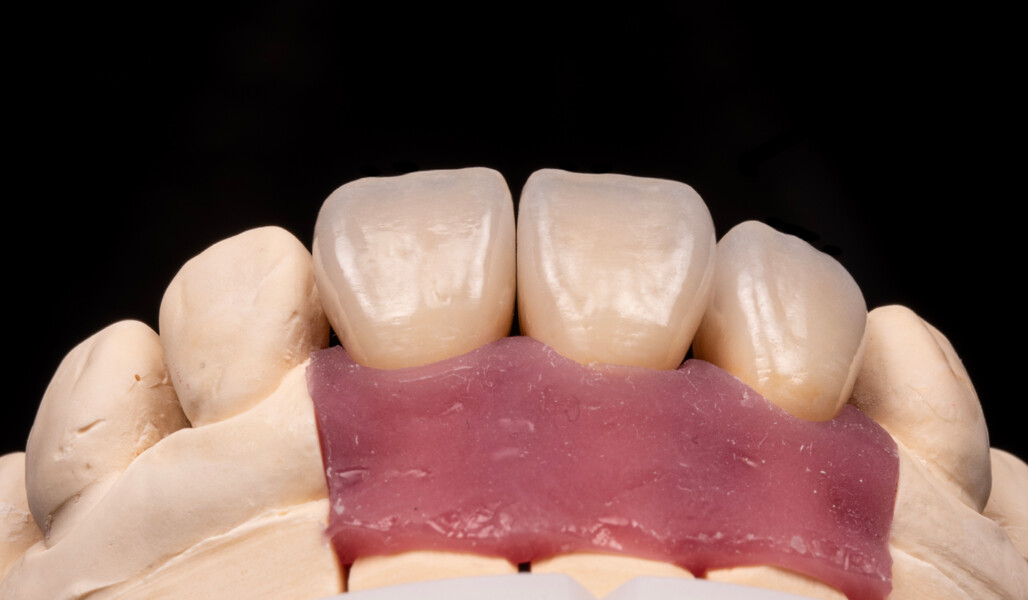

In this article, this point is demonstrated based on the case of a middle-aged female patient who presented with very unsatisfactory metal–ceramic crowns and asked for an aesthetic improvement of the situation (Fig. 1). The crowns on her maxillary central incisors and right lateral incisor clearly needed to be replaced not only for aesthetic reasons but also for functional ones. As anterior interferences were present and orthodontic treatment was not an option, the decision was made to select a ceramic material with a particularly high strength—KATANA Zirconia HT (Kuraray Noritake Dental)—and to opt for a design that would support the incisal edge with zirconia. Consequently, porcelain layering with CERABIEN ZR (Kuraray Noritake Dental) would be limited to the vestibular region (Figs. 2–11).